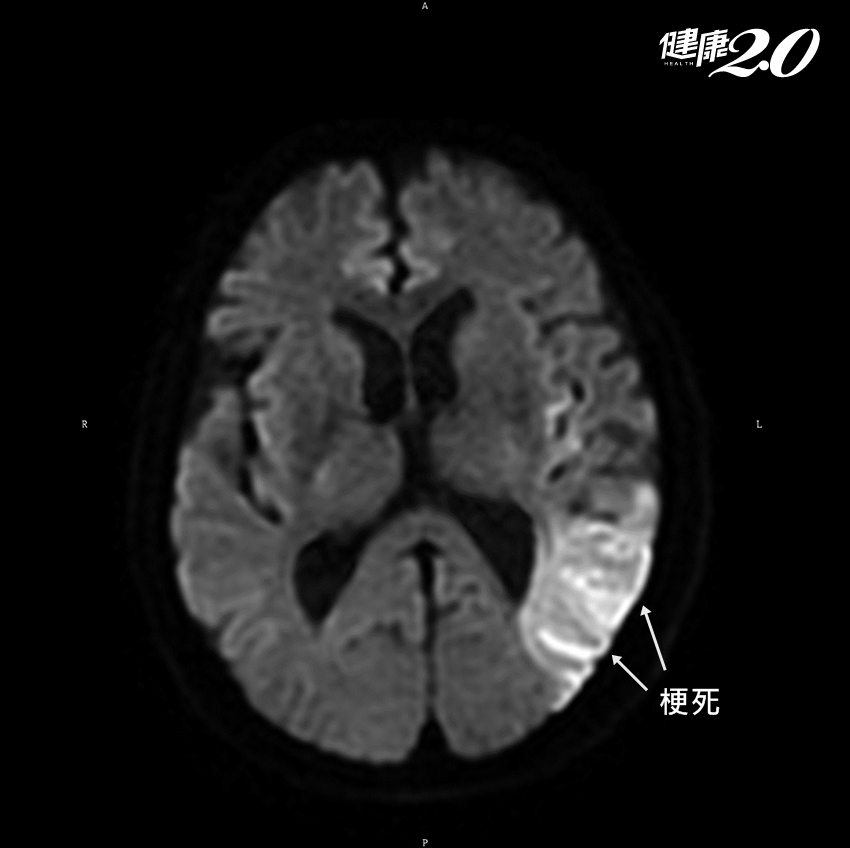

家人覺得奇怪,送他到醫院,一開始以為是精神失常,但做了磁振造影檢查(MRI)後,才發現他的左側的中大腦動脈的分枝血管堵塞,造成左側界於次頂葉及顳葉之間的「語言感覺區」壞死。

簡單來說,就是這次的中風,傷到了他的語言能力。他不是不能說話,而是他的話沒人聽得懂。這一區塊的腦子如果受到損傷,病人雖然說話流利,但幾乎都沒有內容,而且辭不達意,這種現象稱為「Wernicke’s Aphasia」或「感覺失語」症。